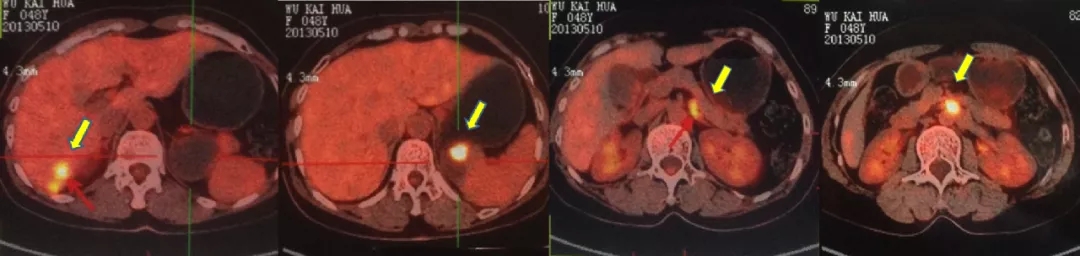

2014.6.11 CT:脾周囊性低密度灶2.4*2.7cm,较2014.2.26增大,腹主动脉旁肿大淋巴结,考虑“卵巢癌复发”。

CT检查结果